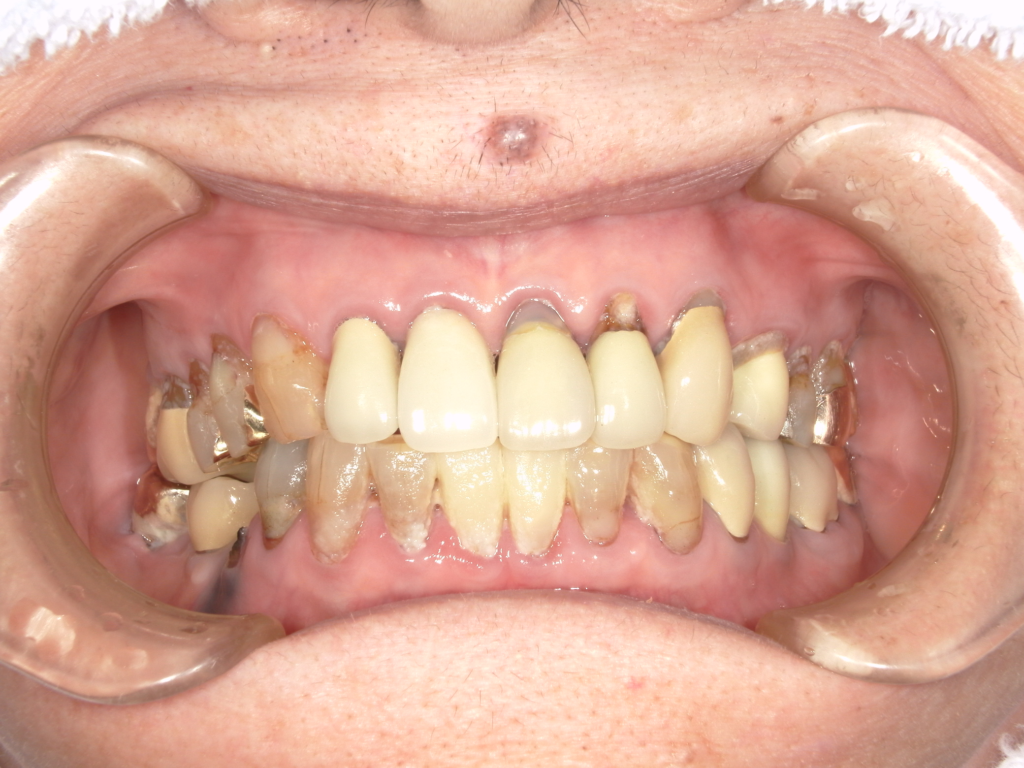

前歯の4本が、残すのが難しい状況となり、インプラント治療を行いました。

インプラントは前歯に2本埋入し、4本の前歯を作っています。歯を抜くと同時にインプラントを埋入し、仮歯を作りました。その後2ヶ月で、被せ物を入れました。被せ物は、セラミックスで作っています。

治療前

治療後